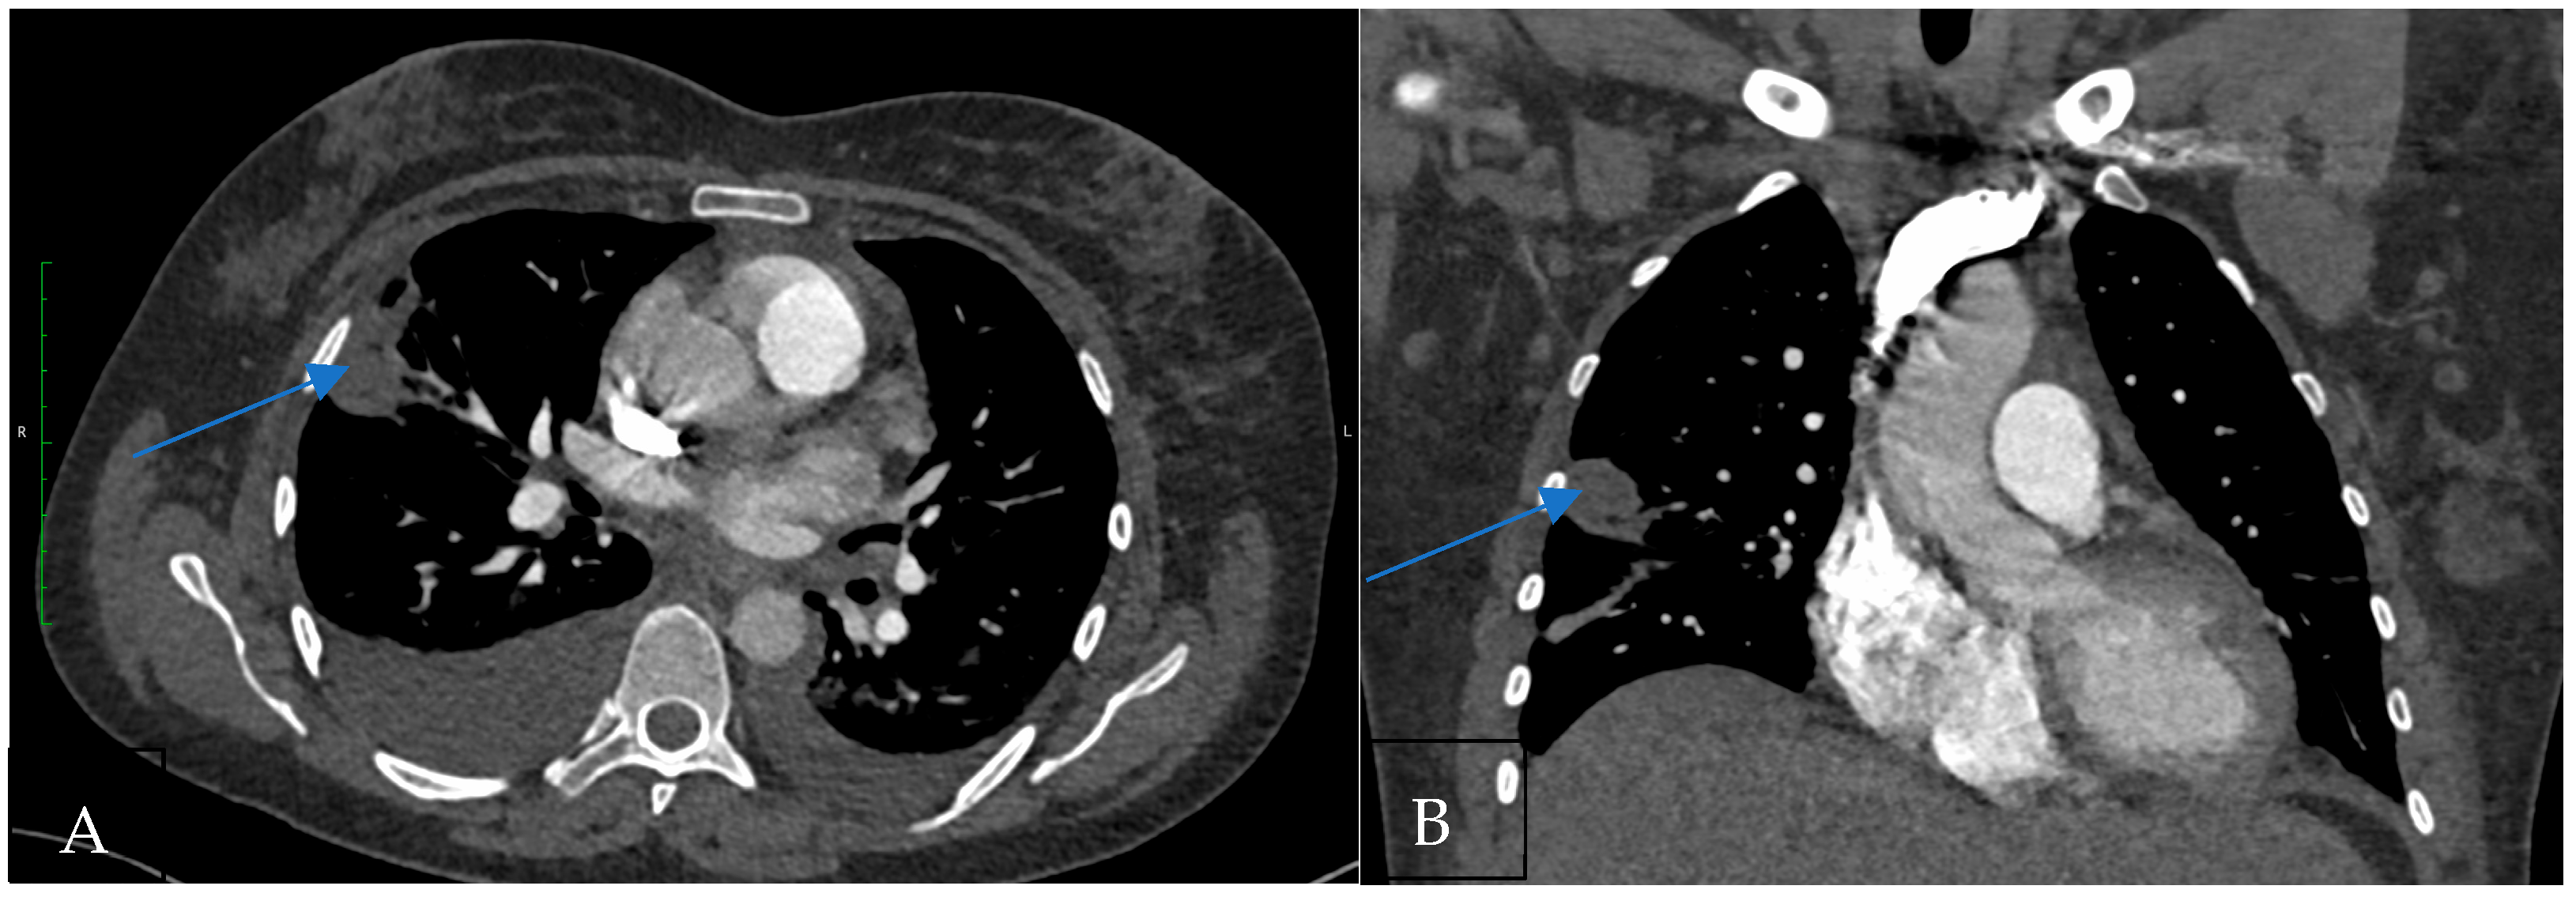

Hampton’s hump (Figure 1) is a radiological finding characterized by a wedge-shaped, peripheral opacification, signifying pulmonary infarction distal to a pulmonary embolus. It is important to emphasize that Hampton’s hump specifically indicates pulmonary infarction secondary to PE rather than PE itself [16].

Figure 1. (A) CT pulmonary angiogram shows the wedge-shaped subpleural pulmonary infarction in the axial plane (Hampton’s hump; arrow). (B) CT pulmonary angiogram shows the wedge-shaped subpleural pulmonary infarction in the coronal plane.